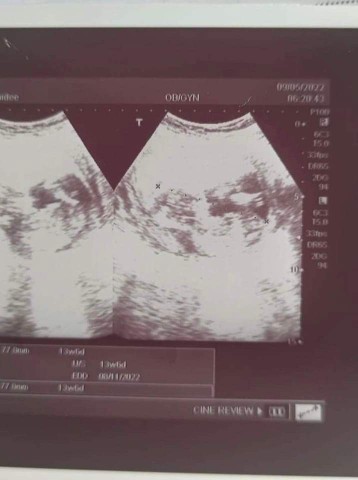

18วีคค่าา ท่าฮิตเลยค่ะแม่

18สัปดาห์

11w5d ค่ะ